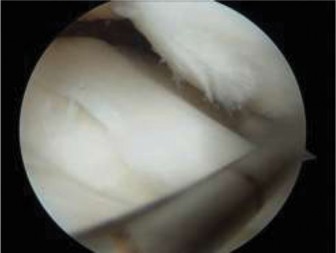

The correct answer is (B). If the patient were asymptomatic, then the discoid meniscus could simply be observed with a return to unrestricted sporting activity. For a younger patient who is intermittently symptomatic and/or elects to not undergo operative intervention, lateral compartment unloader bracing may be appropriate until the patient and/or family agree to intervention. Long-leg casting is not appropriate and will do nothing more than cause stiffness, loss of strength, and range of motion. As the patient is symptomatic, has mechanical symptoms, and has potential tearing seen on MRI, arthroscopic intervention is indicated to examine the meniscus and intervene. The patient is taken to surgery, and intraoperative images ( Figs. 10–31 and 10–32 **) are shown. The next step in management is:**

Figure 10–31

Figure 10–32

The correct answer is (C). The arthroscopic images demonstrate a complete discoid meniscus which is covering the entire lateral tibial plateau. As the patient is symptomatic from the meniscus, saucerization is the first step in management. The meniscus is trimmed back using a combination of shavers and biters to a stable peripheral rim, which replicates the width of the native meniscus. Complete meniscectomy would not be indicated in a patient of this age due to the high risk of early onset degenerative arthritis. In fact, even prior to intervention, many discoid menisci have been associated with the development of lateral hemijoint osteochondral lesions. Although chondroplasty may be necessary, the meniscus is the underlying problem causing chondral wear and must be dealt with first. After saucerization is performed, the meniscus is probed and the following arthroscopic image is seen (Fig. 10–33). The next step in management is: